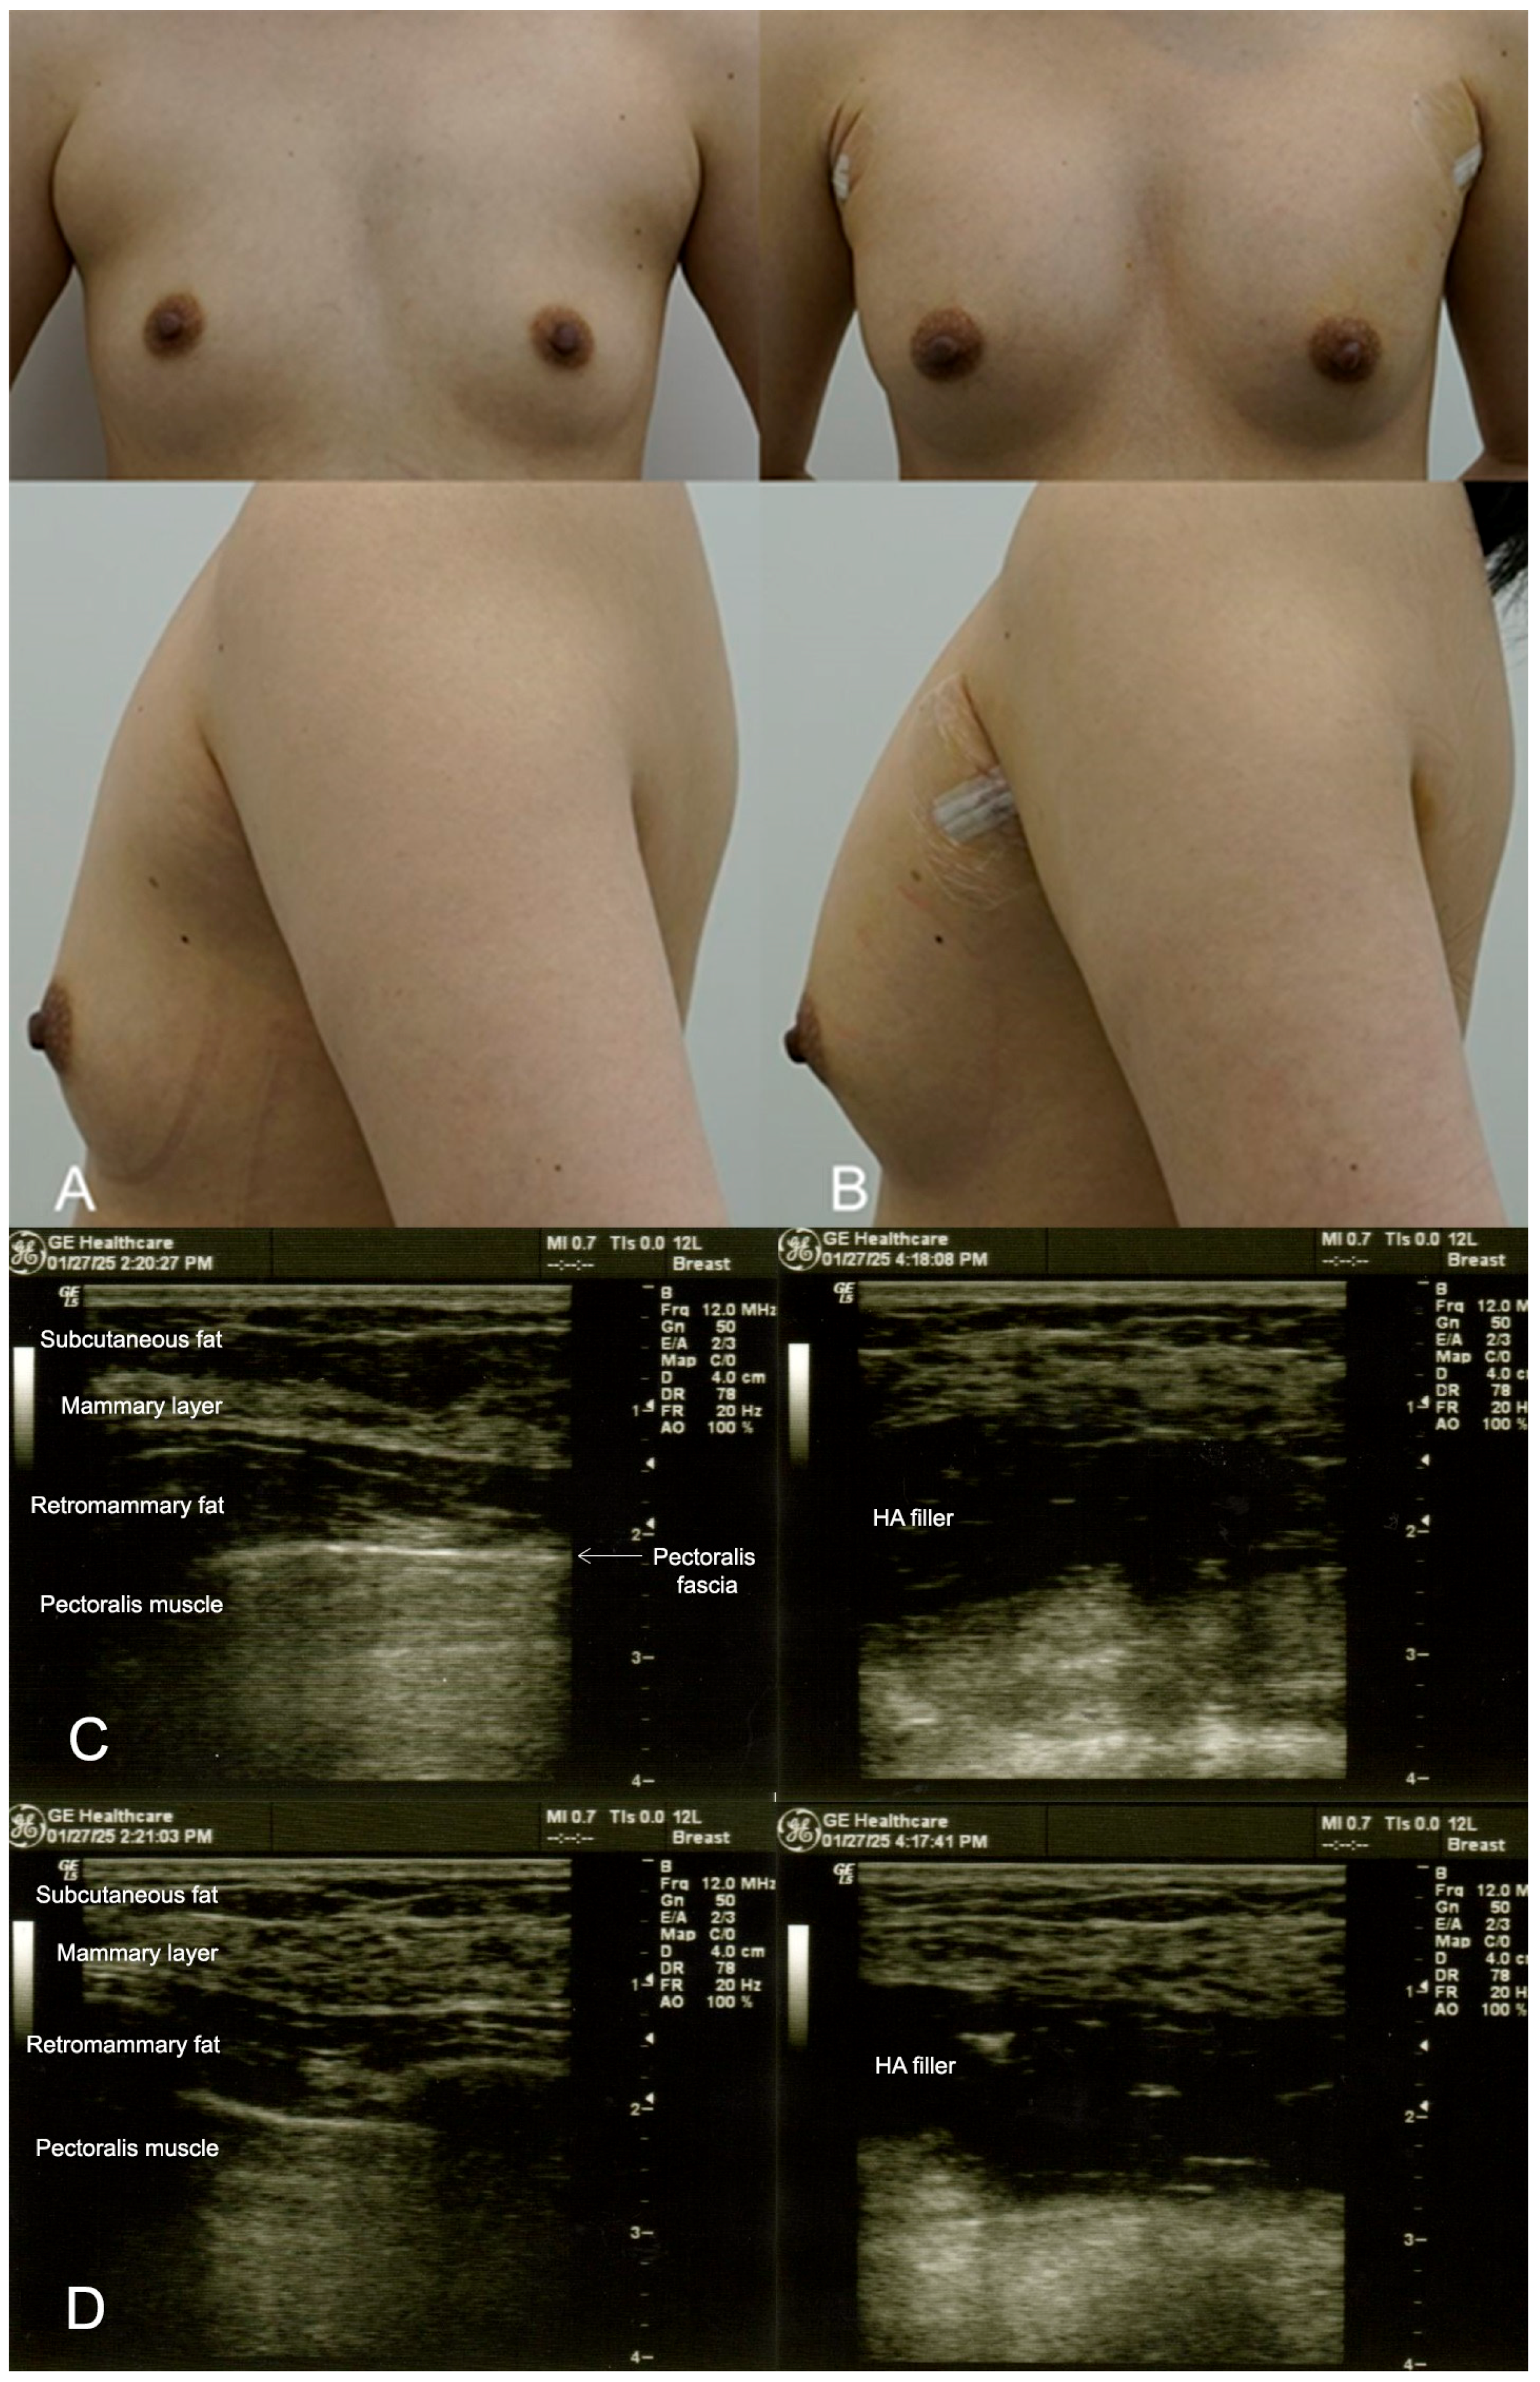

2.1. Case 1: Subtle Enhancement in a 29-Year-Old Female

2.2. Case 2: Moderate Volume Enhancement in a 35-Year-Old Patient with Thin Breast Tissue

2.3. Case 3: Subtle Enhancement for a 32-Year-Old Model

2.4. Case 4: Post-Breastfeeding Volume Restoration in a 36-Year-Old Mother